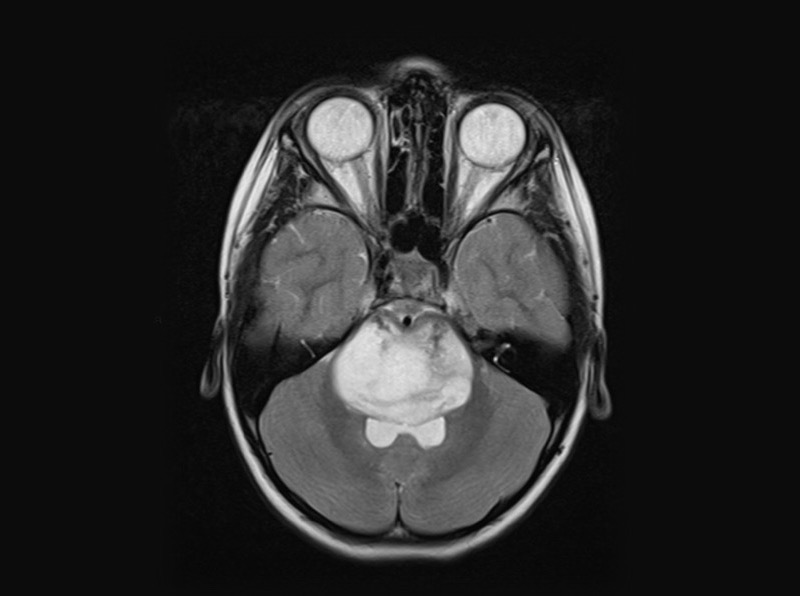

MRI of a diffuse midline glioma